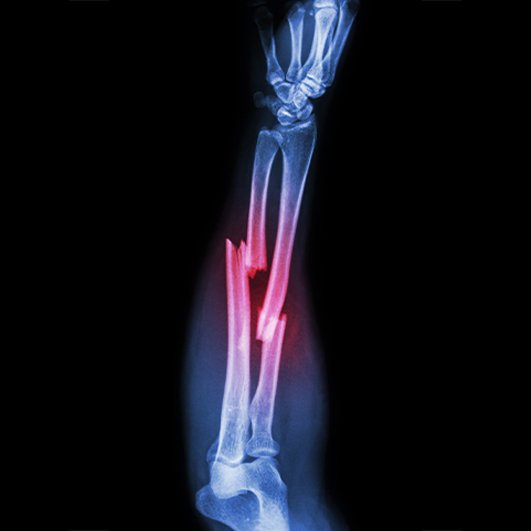

Trauma & Emergency Care

24×7 Orthopedic Trauma Care for fractures and accidents, with immediate surgical and non-surgical treatments ensuring safety and rapid stabilization.